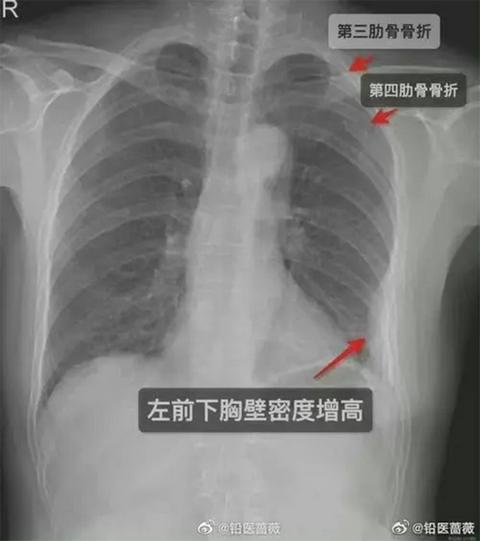

Pet dana nakon izuzetno čvrstog zagrljaja, ženi se pojačao bol u grudima, pa je konačno otišla u bolnicu na pregled. Rendgenski pregled je pokazao da nije imala jedno, već tri slomljena rebra, dva na desnoj strani grudnog koša i jedno na levoj strani!